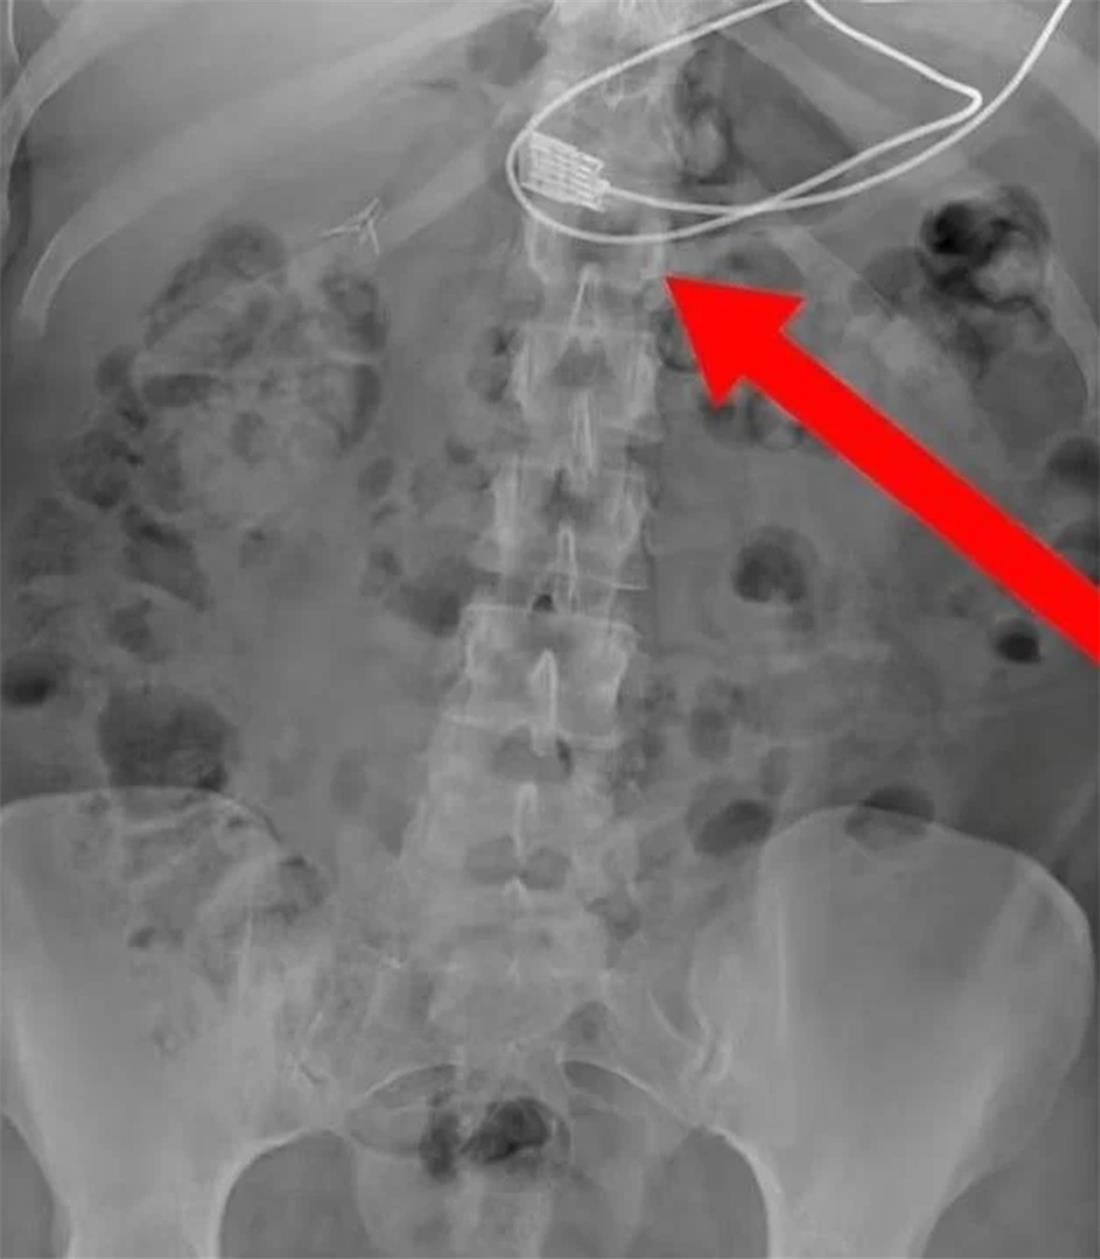

Δημοσιεύοντας μια ακτινογραφία στο Facebook, μια ομάδα με την ονομασία «Ready to Rescue» που διδάσκει Πρώτες Βοήθειες στην πολωνική πόλη Wroclaw ανέφερε: «Η περίπτωση παρουσιάζει μια γυναίκα που κατάπιε ένα καλώδιο φόρτισης (ρεύματος) μήκους ενός μέτρου για ένα iPhone».

«Η γυναίκα κάλεσε την ομάδα διάσωσης μόνο αφού άρχισε να αντιμετωπίζει δύσπνοια λόγω της τοποθέτησης του άνω μέρους του καλωδίου στον οισοφάγο της». Μετά την επέμβαση, η γυναίκα πήρε εξιτήριο από την εντατική.

Η φωτογραφία δημοσιεύτηκε αρχικά στη σελίδα κοινωνικής δικτύωσης μιας ομάδας που αυτοαποκαλείται Savage Paramedics, η οποία περιγράφει τον εαυτό της ως «μια κοινότητα για επαγγελματίες υγείας που συναντιούνται για χιούμορ, διασκέδαση και εκπαίδευση», και πρωτοεμφανίστηκε το Σάββατο.

Συνοδευόταν από μια άλλη φωτογραφία που έδειχνε σε κοντινό πλάνο τον φορτιστή του τηλεφώνου που είχε σφηνωθεί μέσα στο λαιμό της γυναίκας. Στη συνέχεια, η ομάδα δημοσίευσε: «Το καλώδιο αφαιρέθηκε με επιτυχία στο νοσοκομείο και η γυναίκα ανάρρωσε πλήρως».